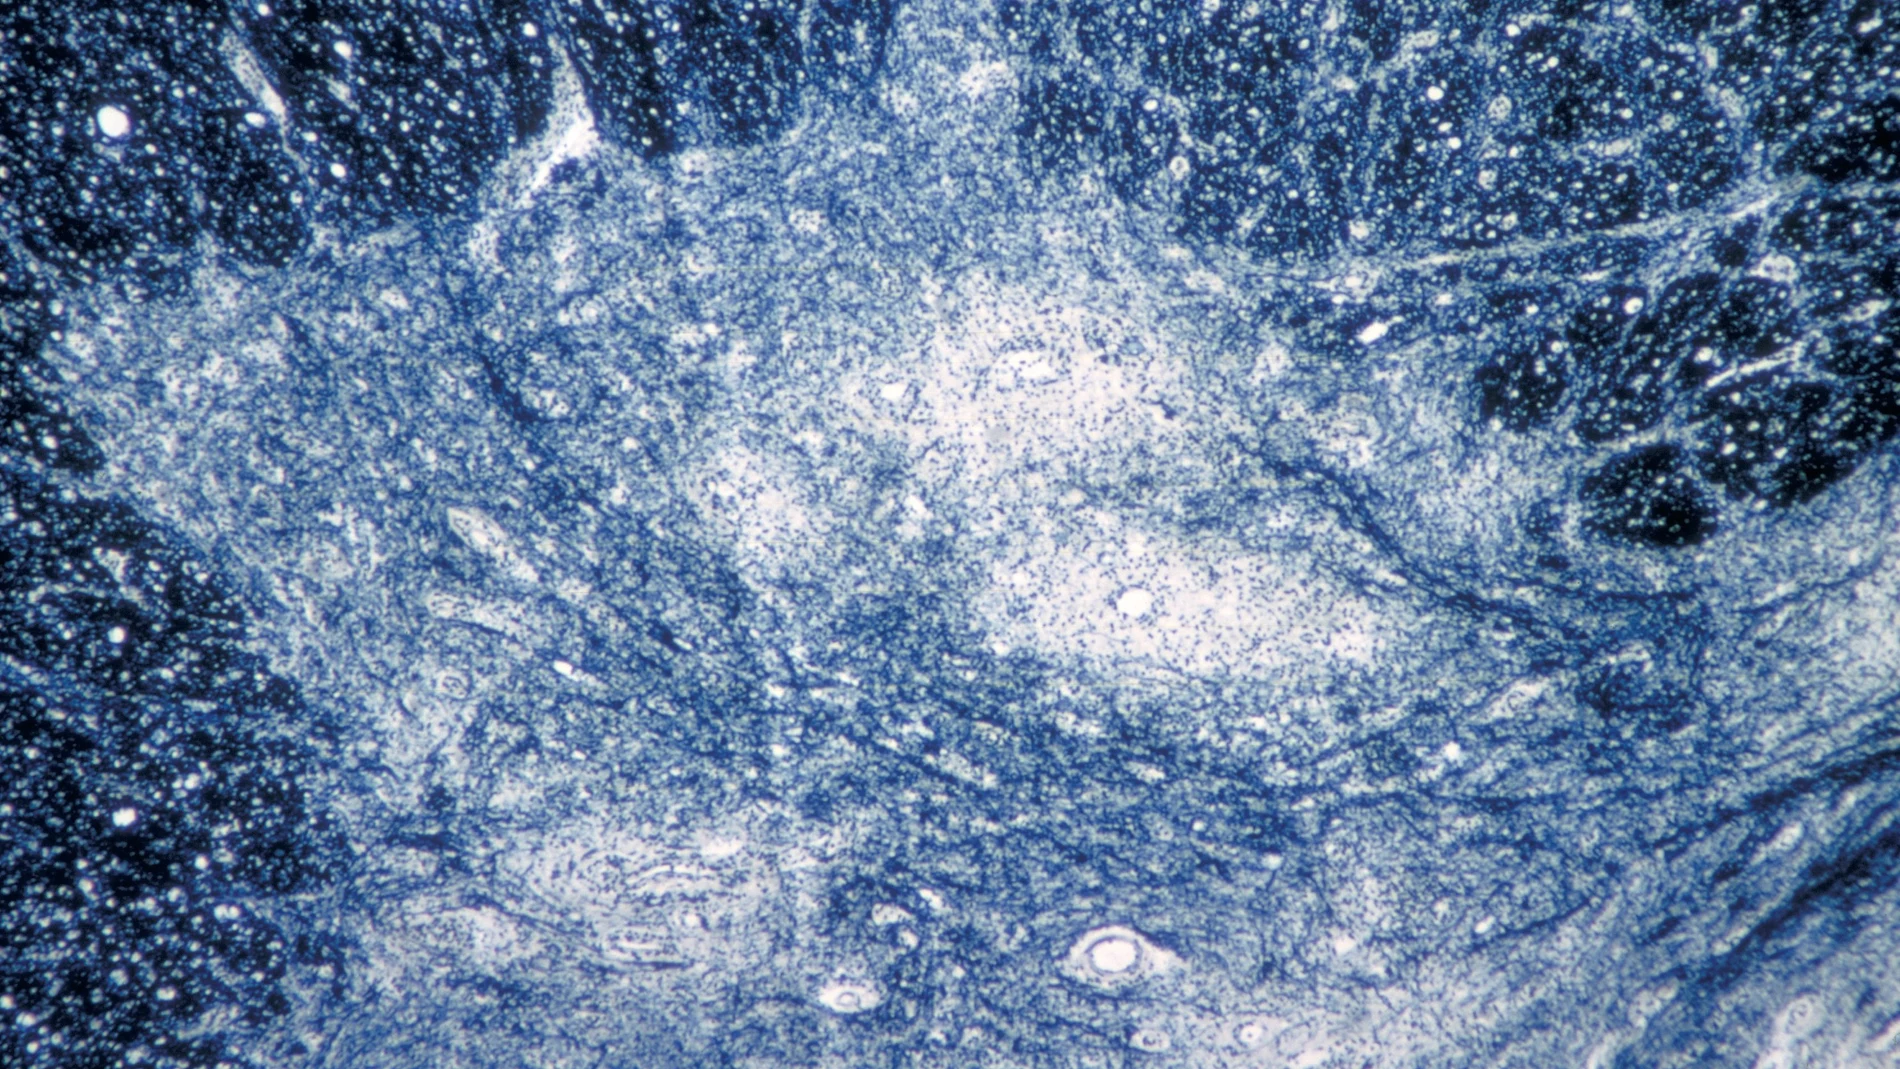

El virus responsable de esta enfermedad se contagia o bien por contacto directo con una persona infectada o, con menor frecuencia, a través de agua y alimentos contaminados. En algunos casos, la infección se presenta de manera asintomática, por lo que las personas afectadas pueden transmitir el virus incluso cuando no parecen enfermas. En otros casos, la polio puede producir síntomas levesparecidos a los de la gripe que pueden tardar hasta 30 días en aparecer.